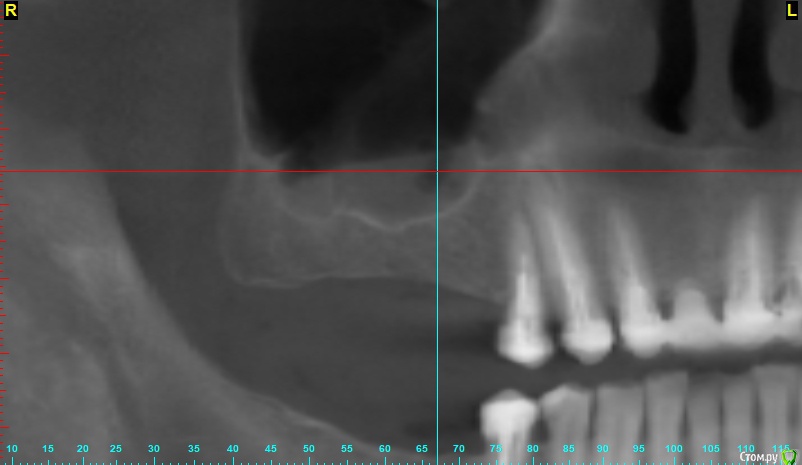

x4ex Опубликовано 7 ноября, 2018 Поделиться Опубликовано 7 ноября, 2018 Добрый день, коллеги! Планируется синус-лифт справа, по словам пациент ЛОР сказал, что противопоказаний не видит. Якобы есть полипы, которые он может убрать эндоскопически, но смысла в этом не видит, потому как со временем они вырастут снова. Но мне картина на КТ похожа не на полипы, а на жидкость с пузырьками воздуха. Кто что думает, стали бы синусить? Ссылка на комментарий

Тимур86 Опубликовано 7 ноября, 2018 Поделиться Опубликовано 7 ноября, 2018 (изменено) я бы 3 коротких поставил. слизистая не гипертрофирована по стенкам-соустье должно открытым быть!ОРВИ во время снимка не было? Изменено 7 ноября, 2018 пользователем Тимур86 1 Ссылка на комментарий

x4ex Опубликовано 7 ноября, 2018 Автор Поделиться Опубликовано 7 ноября, 2018 я бы 3 коротких поставил. слизистая не гипертрофирована по стенкам-соустье должно открытым быть!ОРВИ во время снимка не было? не вижу соустья. ОРВИ говорит не было, на прошлом снимке год назад ещё хуже. Ссылка на комментарий

gum Опубликовано 12 ноября, 2018 Поделиться Опубликовано 12 ноября, 2018 13 и 14 зубы хорошо пролечены? И как граничат с пазухой? Могут ли они провоцировать гайморит? Ссылка на комментарий